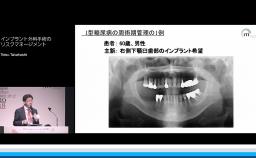

本講演では,上顎洞底挙上術の一手法である側方開窓術の術前臨床的判断基準,術式詳細,臨床経過,CBCT所見,術後偶発症,文献的考察から,開窓部へのバリアメンブレン設置を整理する.

上顎洞底挙上術(術式や合併症など)の理論が理解できる。

上顎洞底挙上術(側方開窓)におけるバリアメンブレンの理論が理解できる。